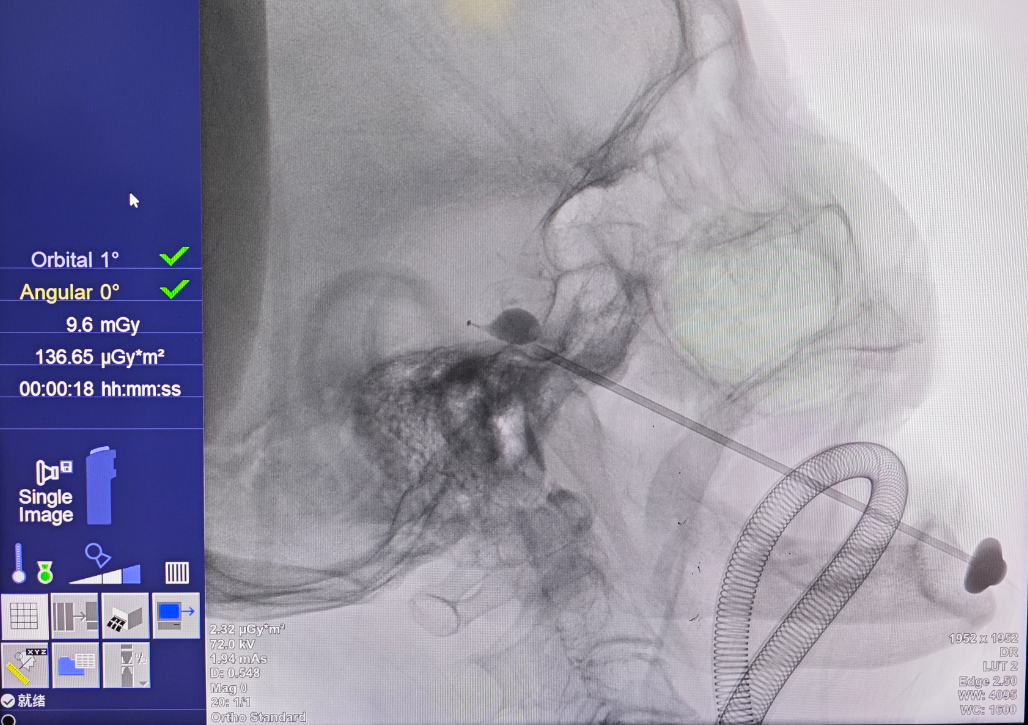

10月16日,手术如期进行。在景主任和赵主任的默契配合下,麻醉、消毒、穿刺等步骤有序推进。然而,就在要把球囊放进指定位置时,陈奶奶突然心跳变慢,情况危急。赵主任马上撤出球囊,麻醉医生迅速处理,仅10秒钟,陈奶奶缓了过来。随后,两位主任再次小心操作,成功完成手术,陈奶奶平安返回病房。